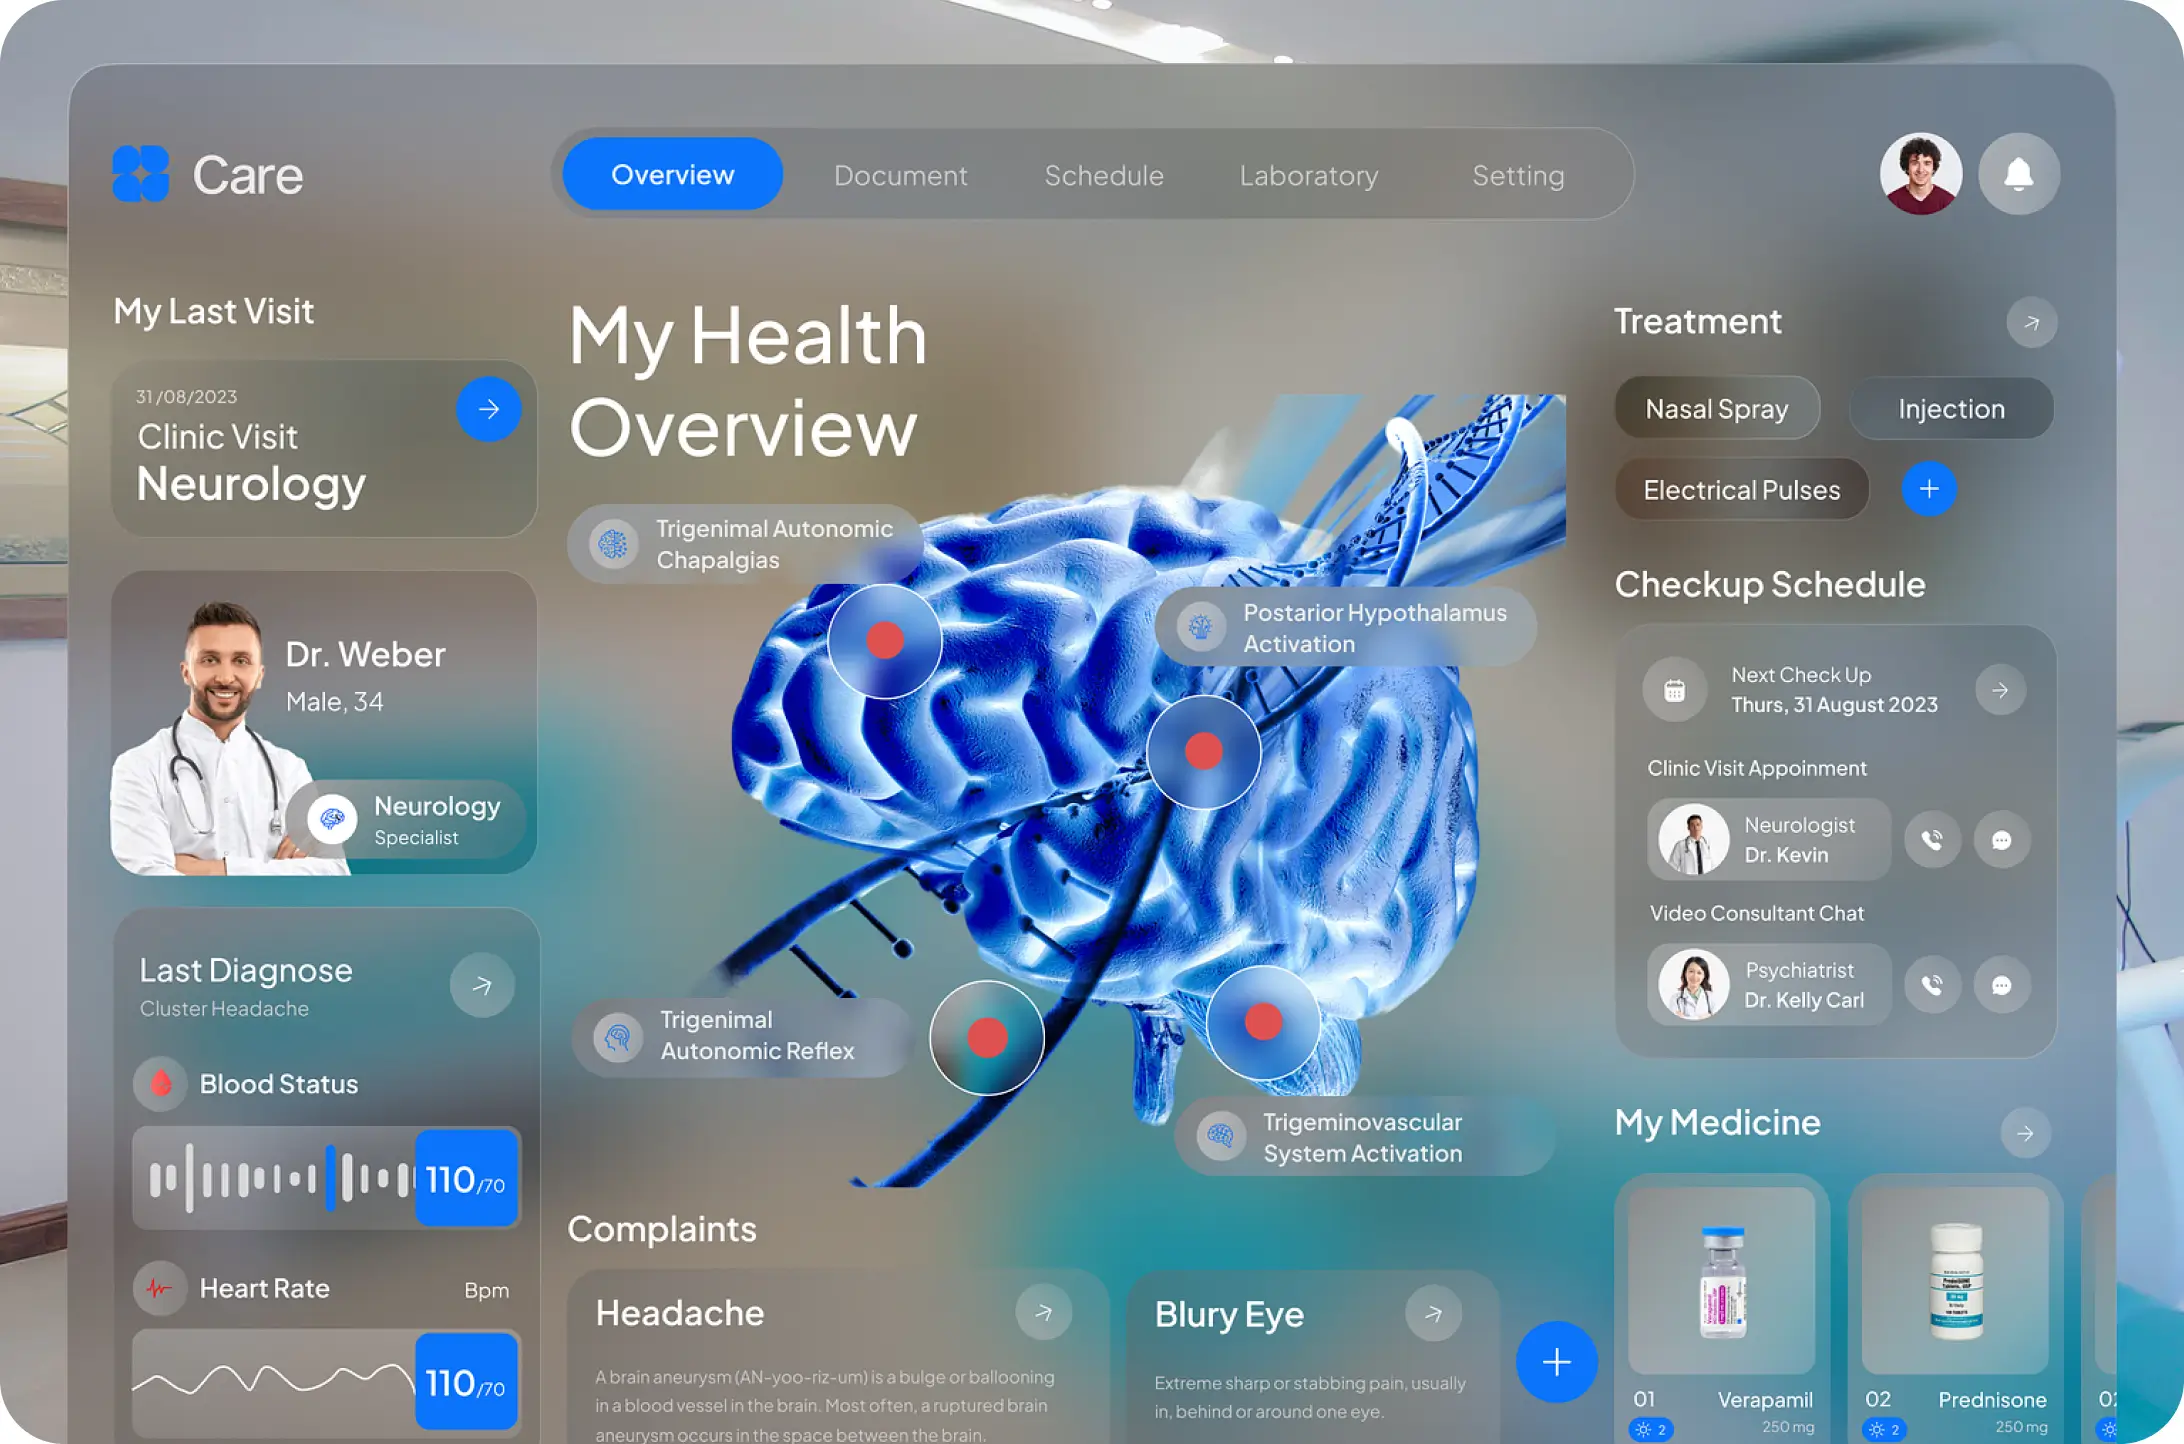

Harnessing AI for Diagnostics and Personalized Treatments

Revolutionizing healthcare with AI-driven diagnostics and personalized treatments for a more precise and innovative medical experience. we reliantly strive to bring about transformative changes in the healthcare sector